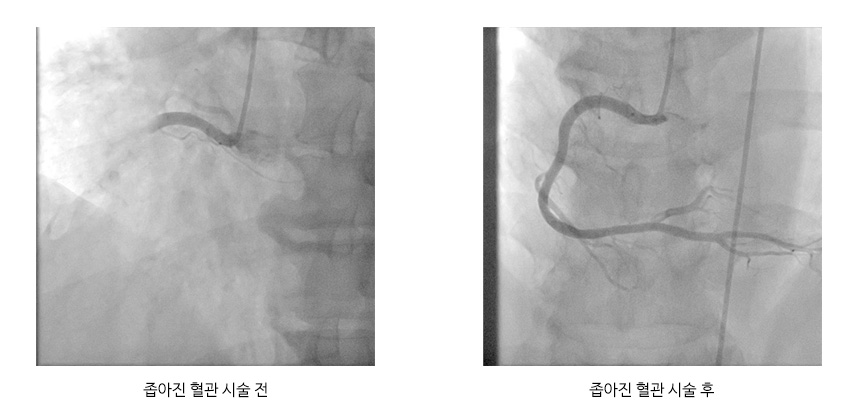

심근경색 의심환자로 병원에 도착하면 채혈 및 심전도검사를 통하여 초기진단을 진행하고 심장초음파를 시행하고 약물 및 환자의 상태에 따라 관상동맥조영술을 통한 풍선성형술을 시행합니다.

X선 영상에서 동맥이 좁아진 상태를 확인